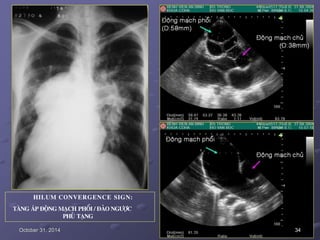

HILUM CONVERGENCE SIGN:

PHÌNH ÑOÄNG MAÏCH PHOÅI (T)

October 31, 2014 D.Anthoine et al.L’Imagerie Thoracique.1996-1998. 33

TAÊNG AÙP ÑOÄNG MAÏCH PHOÅI / ÑAÛO NGÖÔÏC

PHUÛ TAÏNG

October 31, 2014 34